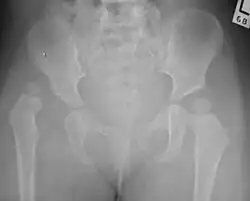

The most useful lines and angles that can be drawn in the pediatric pelvis assessing hip dysplasia are as follows:[50] Different measurements are used in adults.[50]

![Normal hip.[50]](./_assets_/X-ray_of_measurements_on_a_normal_hip.jpg)